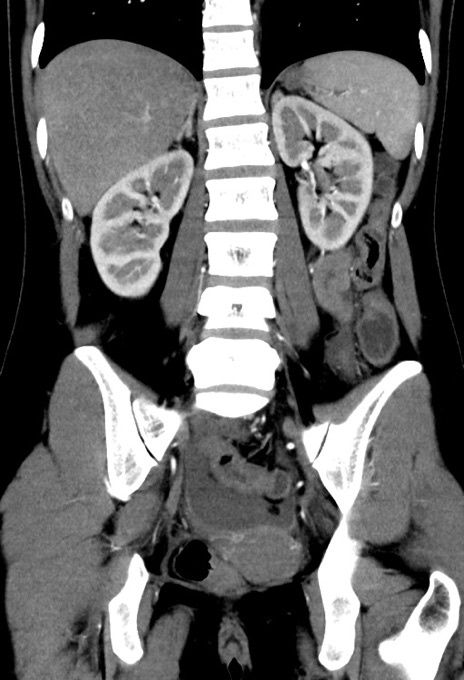

横断像